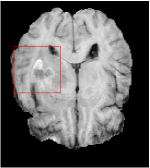

In this section, we test the generalizability of the proposed model that tests on unseen tasks. We fix the well-trained task-invariant parameter and only train for sampling ratios 15%, 25% and 35% with radio masks and sampling ratios 10%, 20%, 30% and 40% with Cartesian masks. In this experiment, we only used 100 training data for each CS ratio and apply a total of 50 epochs. The averaged evaluation values and standard deviations are listed in Table 5.4 and 5.4 for reconstructed T1 and T2 brain images respectively that proceed with radio masks, and Table 5.4 shows the qualitative performance for reconstructed T2 brain image that applied random Cartesian sampling masks. In T1 image reconstruction results, meta-learning improved 1.6921 dB in PSNR for 15% CS ratio, 1.6608 dB for 25% CS ratio, and 0.5764 dB for 35% comparing to the conventional method, which in the tendency that the level of reconstruction quality for lower CS ratios improved more than higher CS ratios. A similar trend happens in T2 reconstruction results with different sampling masks. The qualitative comparisons are illustrated in Figure 2, 4 and 5 for T1 and T2 images tested in skewed CS ratios in radio masks, and T2 images tested in Cartesian masks with regular CS ratios respectively. In the experiments that conducted with radio masks, meta-learning is superior to conventional learning especially at CS ratio 15%, one can observe that the detailed region in red boxes keeps edges and is more close to the true image, while conventional method reconstructions are hazier and lost details in some complicated tissue. The point-wise error map also indicates that Meta-learning has the ability to suppress noises.

Training with Cartesian masks is more difficult than radio masks, especially for conventional learning where the network is not very deep since the network only applied three convolutions each with four kernels. Table 5.4 indicates that the average performance of meta-learning improved about 1.87 dB comparing to conventional methods with T2 brain images. These results further demonstrate that meta-learning has the benefit of parameter efficiency, the performance is much better than conventional learning even if we apply a shallow network with small size of training data.